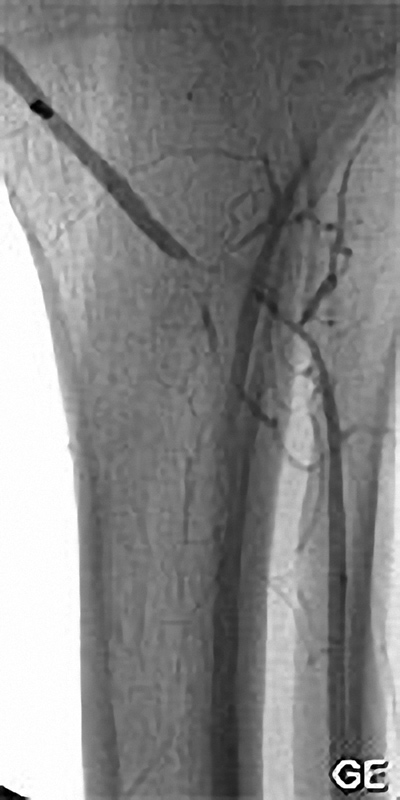

Einengung einer Beckenarterie

Die PTA (Perkutane Transluminale Angioplastie) im Beckenbereich ist ein minimalinvasives Verfahren zur Behandlung von verengten Beckenarterien. Dabei wird ein dünner Katheter mit einem Ballon über die Leiste in die verengte Arterie eingeführt. Der Ballon wird an der Engstelle entfaltet und dehnt die Arterie auf, um den Blutfluss zu verbessern. Oft wird zusätzlich ein Stent eingesetzt, um die Arterie dauerhaft offen zu halten. Die PTA wird meist in örtlicher Betäubung durchgeführt und ermöglicht eine schnelle Erholung. Sie ist eine bewährte Alternative zur offenen Operation bei Durchblutungsstörungen im Becken- und Beinbereich.